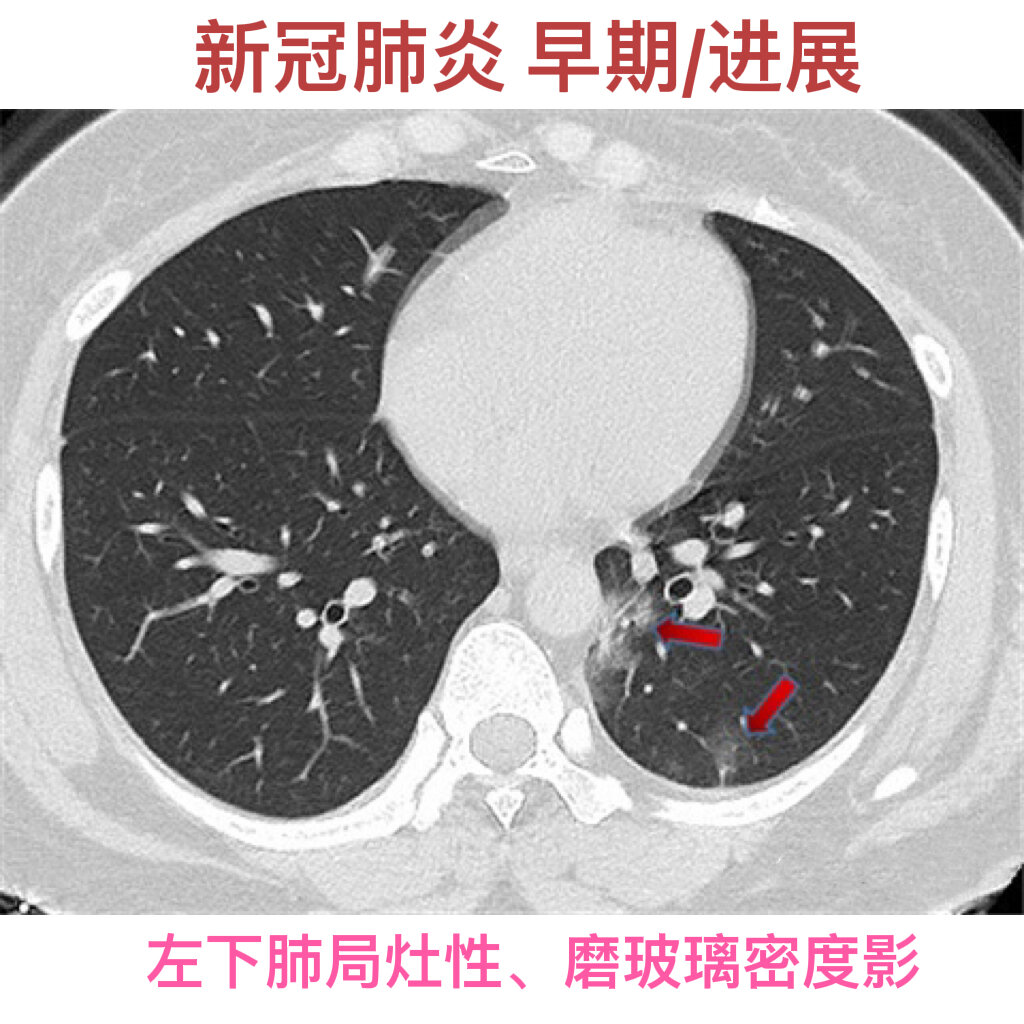

p>新冠肺炎的ct影像学表现 br>新冠肺炎即新型冠状病毒肺炎 br> br>